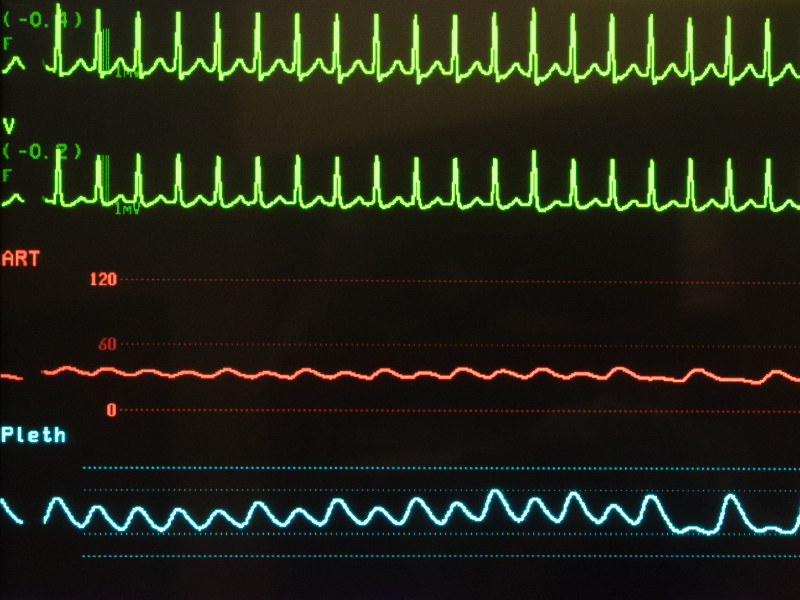

Infarto oculto

Certa vez, atendi na sala de emergência um paciente colega médico que chegou deambulando e se queixando de palpitações taquicárdicas. De fato, sua FC à palpação do pulso se mostrava elevada e logo deitei o paciente na maca.

Enquanto ele era monitorizado, ele revelou que as palpitações haviam se iniciado na manhã daquele dia – iniciei o atendimento por volta das 16h! – e que ele havia permanecido dessa forma até o momento. Negava dor torácica, sinais de baixo débito ou qualquer outra queixa.

Realizado o ECG, foi identificada uma taquicardia supraventricular paroxística e realizada a infusão de adenosina para reversão, realizada com sucesso. Até aí, tudo bem.

A minha maior surpresa foi quando solicitei o ECG de controle pós-reversão do ritmo para ritmo sinusal e encontrei no traçado uma área eletricamente inativa extensa em parede anterior, antes não vista de forma clara por causa da arritmia.

Figura 8: Sempre faça o ECG de controle após a reversão de uma taquicardia supraventricular paroxística.

Figura 8: Sempre faça o ECG de controle após a reversão de uma taquicardia supraventricular paroxística.

Nesse momento, fui obrigado a revisitar a história do paciente e interrogar ativamente a ocorrência de qualquer sintoma que pudesse justificar a possibilidade de um infarto prévio.

Inicialmente ele negou qualquer sintoma de dor torácica, mas insisti e ele recuperou da memória um episódio de dor torácica que ele denominou de costocondrite (uma inflamação da cartilagem que conecta a costela ao osso esterno) que ocorreu justamente após um esforço físico (jogo de tênis) e que ele mesmo “tratou” com infusão de um anestésico local.

Na hora, diagnostiquei aquele evento como IAM prévio recente, associando a história aos achados descritos no ECG de repouso em ritmo sinusal. Ou seja, a interpretação do achado foi feita adicionando o elemento clínico e orientando melhor a próxima tomada de decisão.

Imagine se eu não tivesse insistido em questionar sobre a história clínica. Imagine deixar passar um diagnóstico tão importante.

O paciente foi admitido, submetido a ecocardiograma que mostrou insuficiência ventricular esquerda secundária a acinesia importante da parede livre do ventrículo esquerdo. Felizmente, foi submetido a revascularização após pesquisa de viabilidade miocárdica e acabou evoluindo bem.

Figura 7: IAM de parede anterosseptal: elevação do segmento ST de V1 a V3. Figura 8: Sempre faça o ECG de controle após a reversão de uma taquicardia supraventricular paroxística.

Figura 8: Sempre faça o ECG de controle após a reversão de uma taquicardia supraventricular paroxística. Figura 9: IAM de parede inferior. Considerar infarto de VD e providenciar ECG com derivações direitas V3R e V4R.